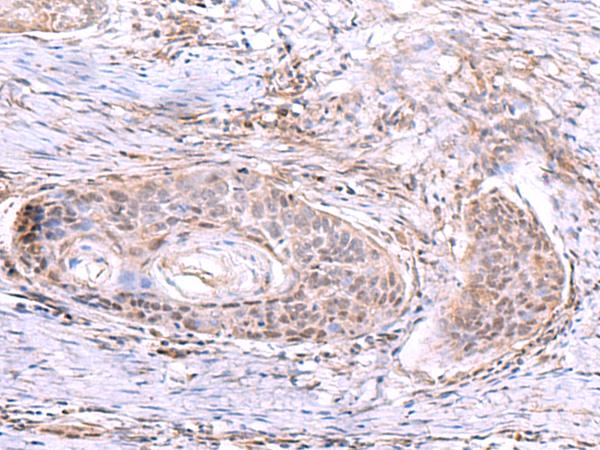

分类: 科研抗体货号: P03309别名: PSF3应用: WB,IHC反应种属: Human, Mouse